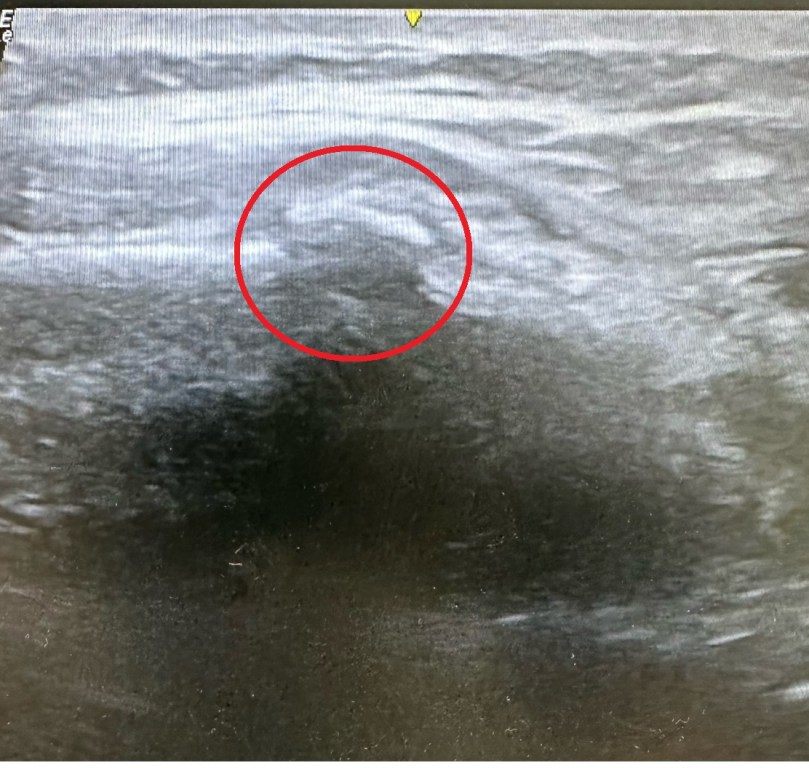

骨骼掃描或核磁共振是檢測壓力性骨折的最佳方法,儘管可能需要幾個月的時間才能有骨痂形成的真實證據。超音波檢查也可用於診斷。

↑這是今天一位划龍舟的個案超音波下的腹外斜肌與被拉起來的肋骨